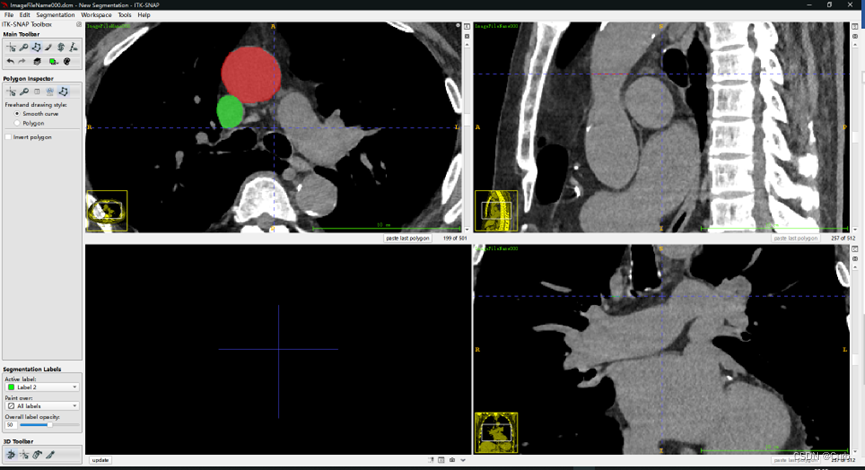

对不同部位使用不同的标签,点击上图中的圈出位置,进行切换标签(颜色不同)。标注之后的效果如下:

在这里我连续标注了多张,只选择了两个区域,相当于用了两种标签,效果如下

容易发现三个方向的图都有对应的标签。通过点击下图圈出的update会生成3D的标签图: